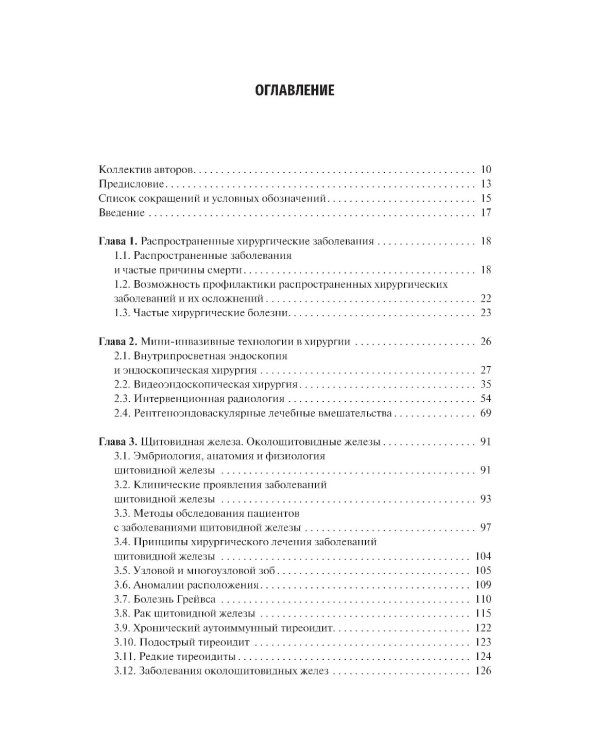

Содержание учебника соответствует программе по факультетской и госпитальной хирургии, а также квалификационной характеристике врача по специальности «Хирургические болезни» и включает главы по хирургической гастроэнтерологии, пульмонологии, кардиологии, ангиологии, флебологии и эндокринологии. В работе над ним принимали участие ведущие специалисты медицинских вузов, институтов РАН, клинических и научно-исследовательских центров. Издание предназначено для самостоятельной теоретической подготовки студентов старших курсов лечебного и педиатрического факультетов медицинских вузов, а также клинических ординаторов и аспирантов системы последипломного образования.| Издательство | ГЭОТАР-Медиа |